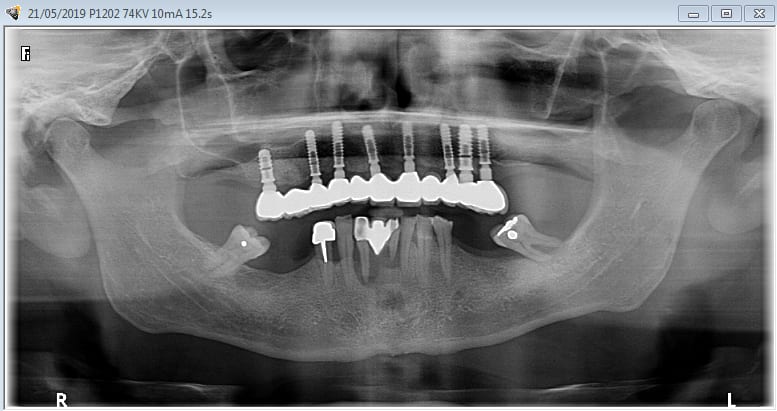

La vidéo présente à partir des plans de traitements, des chirurgies de beotien , des dispositifs médicaux sur mesure positdental et positguide la mise en charge immédiate post-extractionnelle d’un bridge provisoire à armature métal en prothèse fixe sur implants cône morse donc sans vis de maintien. Une question est émise « comment obtient-on ce résultat ? ». Une partie des réponses comme la prédictibilité, la reproductibilité peuvent y être déduite pour d’autre il faudra la bonté de beotien de faire partager les résultats clinique.il nous fait la générosité de poster la phase cicatriciel à 7 jours et des photos de la chirurgie sur un cas.

planif cas 1

contrôle d'un des cas à 1 mois

24/05/2019 à 18h53

Je viens de revoir au cabinet un des 3 cas, car la céramique de la 25 était fracturée.

J'ai pris une photo (iphone) avec le bridge déposé avant de mettre temporairement le bridge coping de Posit. Pas la peine de commenter le bas je n'en suis pas responsable.